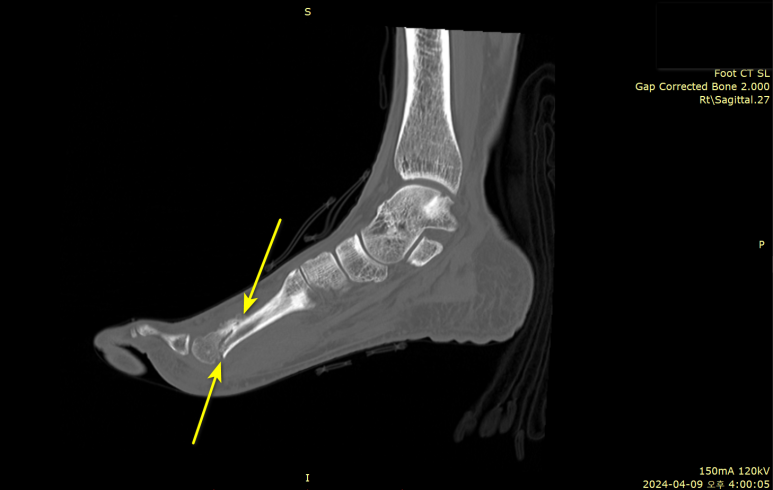

640 CT 정밀검사 시행

급성 골절(骨折)을 확진하려면CT 같은 방사선 검사가 필요합니다.

특히 640 CT로

촘촘하게 슬라이스해보면

미세골절도 찾을 수 있거든요.

해당 환자분은

CT 정밀검사상두번째 중족골 골절로최종 진단되었습니다.

골절된지도 모르고

많이 걸으셔서

뼈가 살짝 어긋난 부분도 있었는데요.

영상으로 보시면

발등면부터 발바닥까지

쭉 골절되셨셨고요.